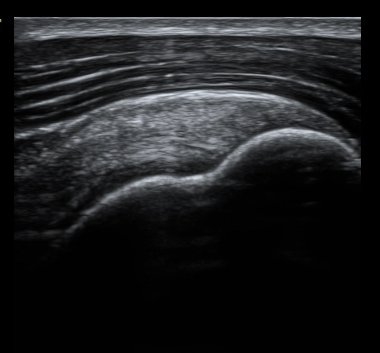

°üÂûµÊ(±×¸² 3, 4). °ß°©ÇÏ±Ù°Ç È¾´Ü¸é°Ë»ç¿¡¼­µµ °ß°©Çϱٰdz» °£±ØÀÌ °üÂûµÊ(±×¸² 5).

±Ø»ó°Ç Á¾´Ü¸é°Ë»ç¿Í Ⱦ´Ü¸é°Ë»ç¿¡¼­ ±Ø»ó°Ç³» ¹Ì¼¼ÇÑ °£±ØÀÌ °üÂûµÊ(±×¸² 6, 7, 8).